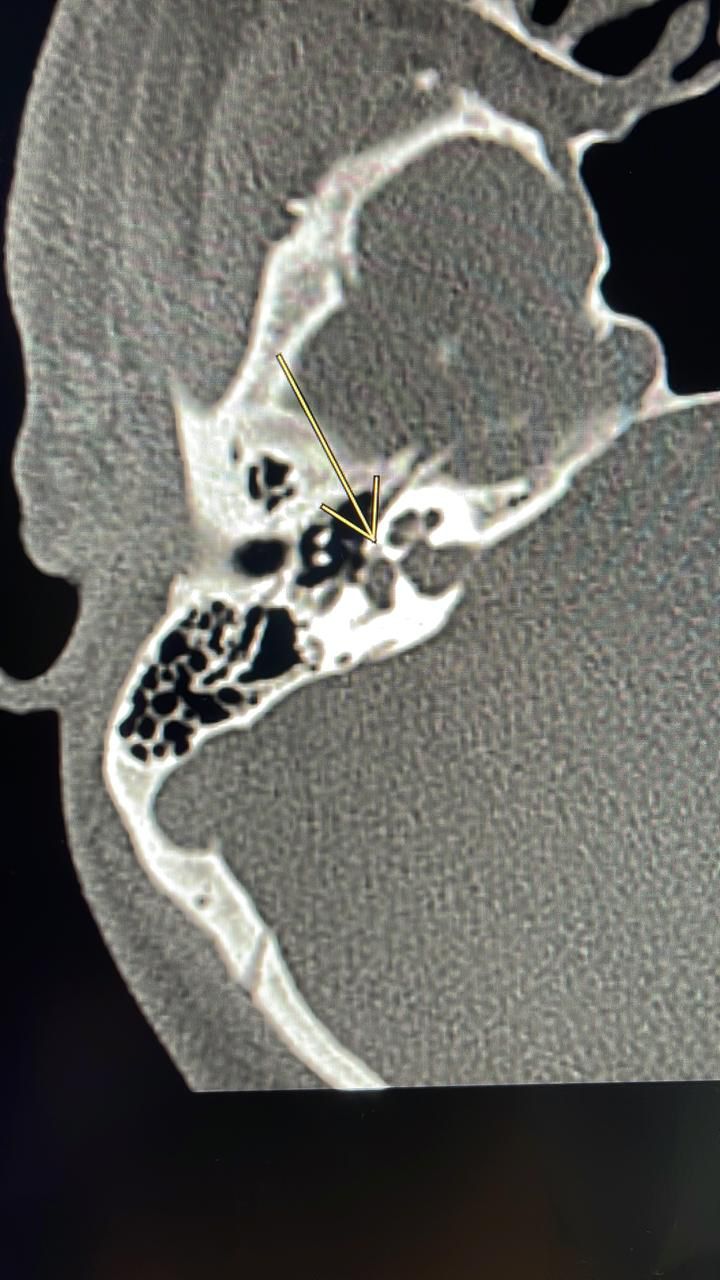

أسهم بفضل الله فريق طبي بمركز الرأس والعنق وقاع الجمجمة بمدينة الملك عبدالله الطبية بمكة المكرمة في إنهاء معاناة شاب من ضعف السمع ، حيث تبين بعد إجراء كامل الفحوصات الطبية اللازمة وجود تصلب عظمة الركاب والذي تسبب بانعدام وجود الاهتزازات التي تنقل الصوت نتيجة نمو العظم حول الصفيحة القدمية لعظمة الركاب مما يتسبب في فقدان تدريجي للسمع.

وقد قرّر الفريق الطبي إجراء جراحة مجهرية بتقنية المايكروسكوب عن طريق ثقب لعظمة الركاب المتصلبة و تركيب عظمة صناعية بديلة وذلك تحت التخدير الموضعي حيث كانت استجابة المريض للعلاج في نفس الوقت وذلك لكونه في كامل وعيه مما أتاح الفرصة لملاحظة التحسن في السمع مع غياب أي مضاعفات من هذا الإجراء الجراحي، وقد تكلّلت العملية بالنجاح ولله الحمد وأستغرقت ساعة واحدة ليخرج بعدها الشاب بصحة وعافية وتتم متابعة حالته بالعيادات الخارجية.